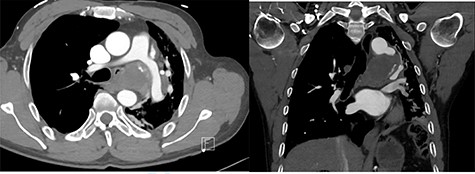

On presentation, chest X-ray illustrated a prominent proximal descending thoracic aorta contour and a completely collapsed left lung (Fig. 1). On computed tomography angiogram (CTA), the patient was found to have a large saccular aneurysm measuring 5.0 × 5.0 × 5.0 cm in size, arising from a focal location of the proximal descending thoracic aorta distal to the origin of the left subclavian artery with evidence of contained rupture (Fig. 2). The mass was found to be causing significant external compression of the left main bronchus leading to significant effacement of the left main primary bronchi leading to extensive collapse in both left upper and lower lobes and overall reduction in volume of the left hemithorax (Fig. 3).

Repeat CTA illustrated good flow through the thoracic aneurysm, re expansion of the left lung, and decompression of the left main bronchus. Histopathology of washing and fine needle aspirates was all negative for tuberculosis and bacteria. Histopathology revealed fibroid and necrotic material with mixed acute and chronic inflammatory changes, fragments of benign bronchial epithelium and ulceration and squamous metaplasia; no granulomas were present. Further, nil malignancy was detected.